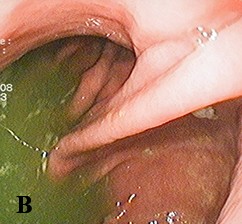

Диагностика ДГР при ЭГДС легко устанавливается по наличию желтого, зеленого окрашивания содержимого желудка, т. е. по наличию желчи в желудочном соке. Желтое содержимое желудка соответствует легкой степени (см. рис. 1а); прозрачное светло-зеленое — средней степени (см. рис. 1б) и мутное темно-зеленое — тяжелой степени рефлюкса (см. рис. 1в). ЭГДС не может провоцировать ДГР, так как интубация пищевода и прохождение эндоскопа по пищеводу занимает несколько секунд. Факт поступления желчи из привратника не является физиологическим и не может быть классифицирован как истинный ДГР.

Рис. 1. Степени тяжести ДГР при ЭГДС.